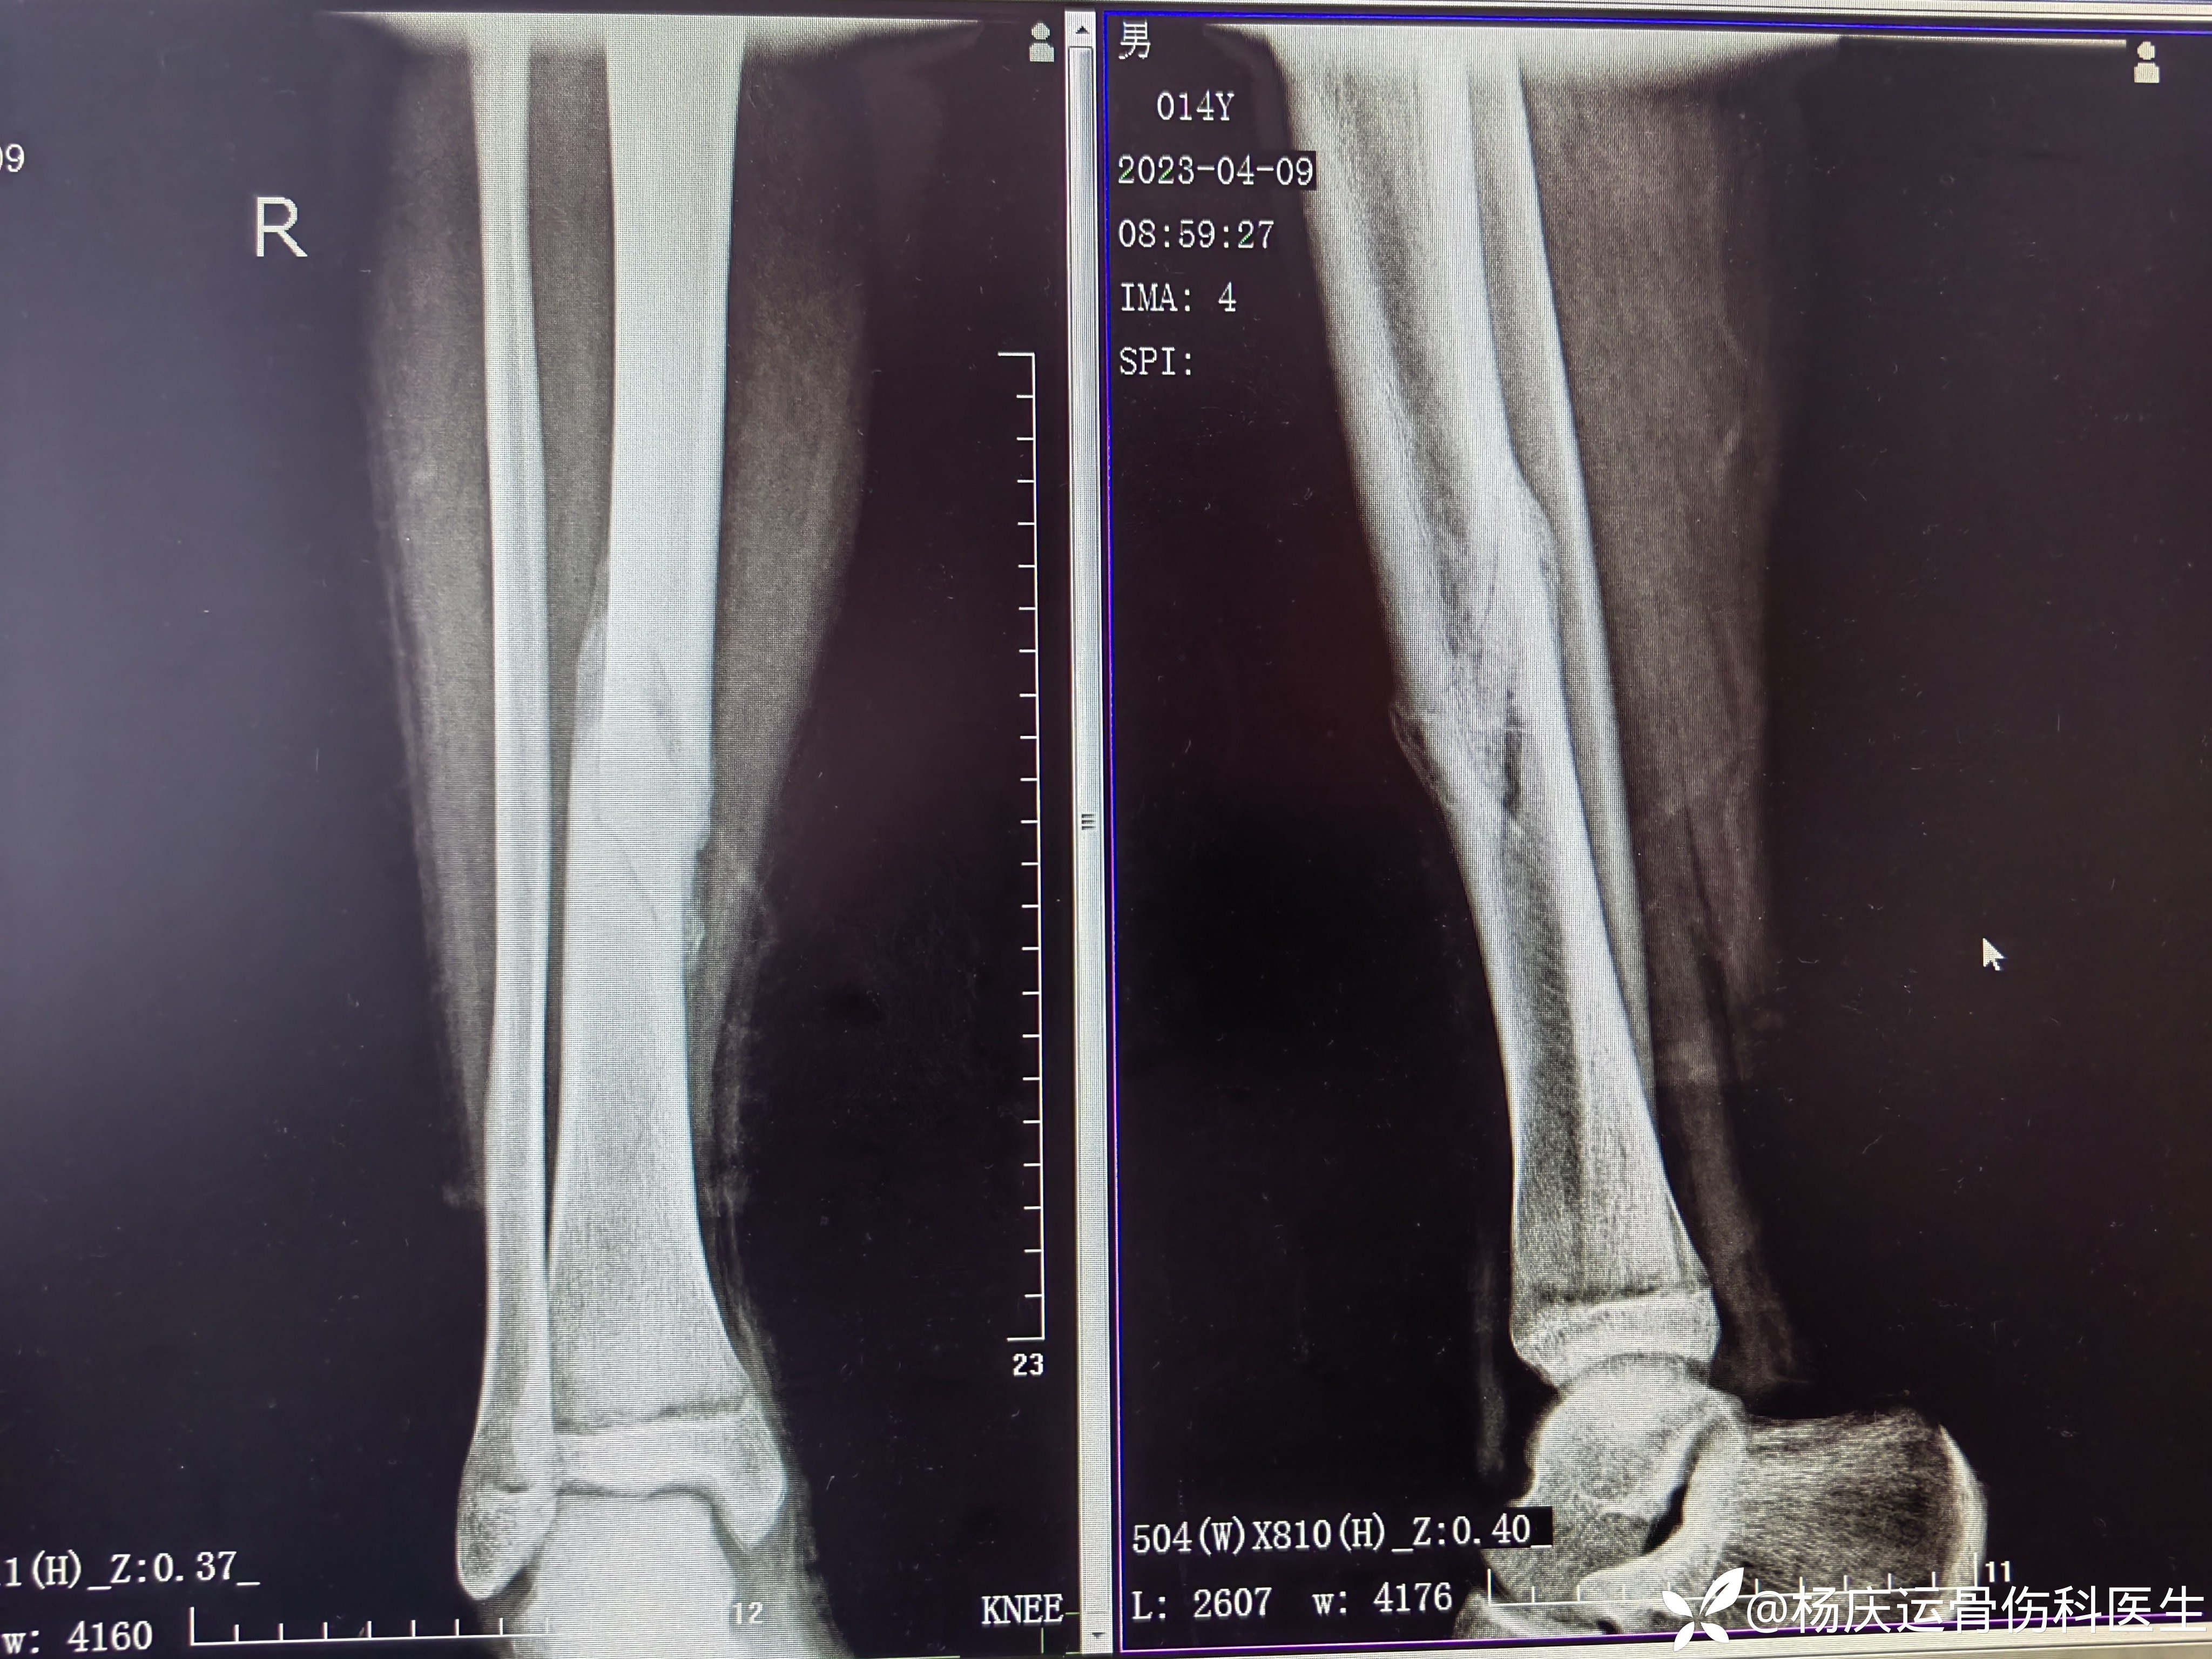

8.5个月复查,愈合良好,力线正常

功能恢复正常